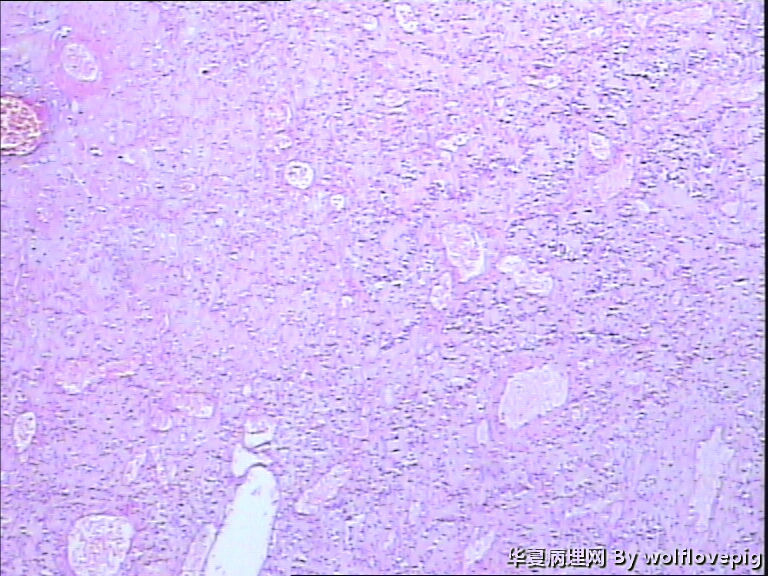

求助!肌瘤变性?

上皮样平滑肌瘤,鉴别PECOMA

平滑肌瘤伴间质玻璃样变性,像是冰冻的片子吧?》

常规石蜡切片

上皮样平滑肌瘤

像平滑肌瘤玻璃变性

符合平滑肌瘤伴梗死,多取材寻找有无质软,肉质样变区,破碎的组织最麻烦,要慎重。